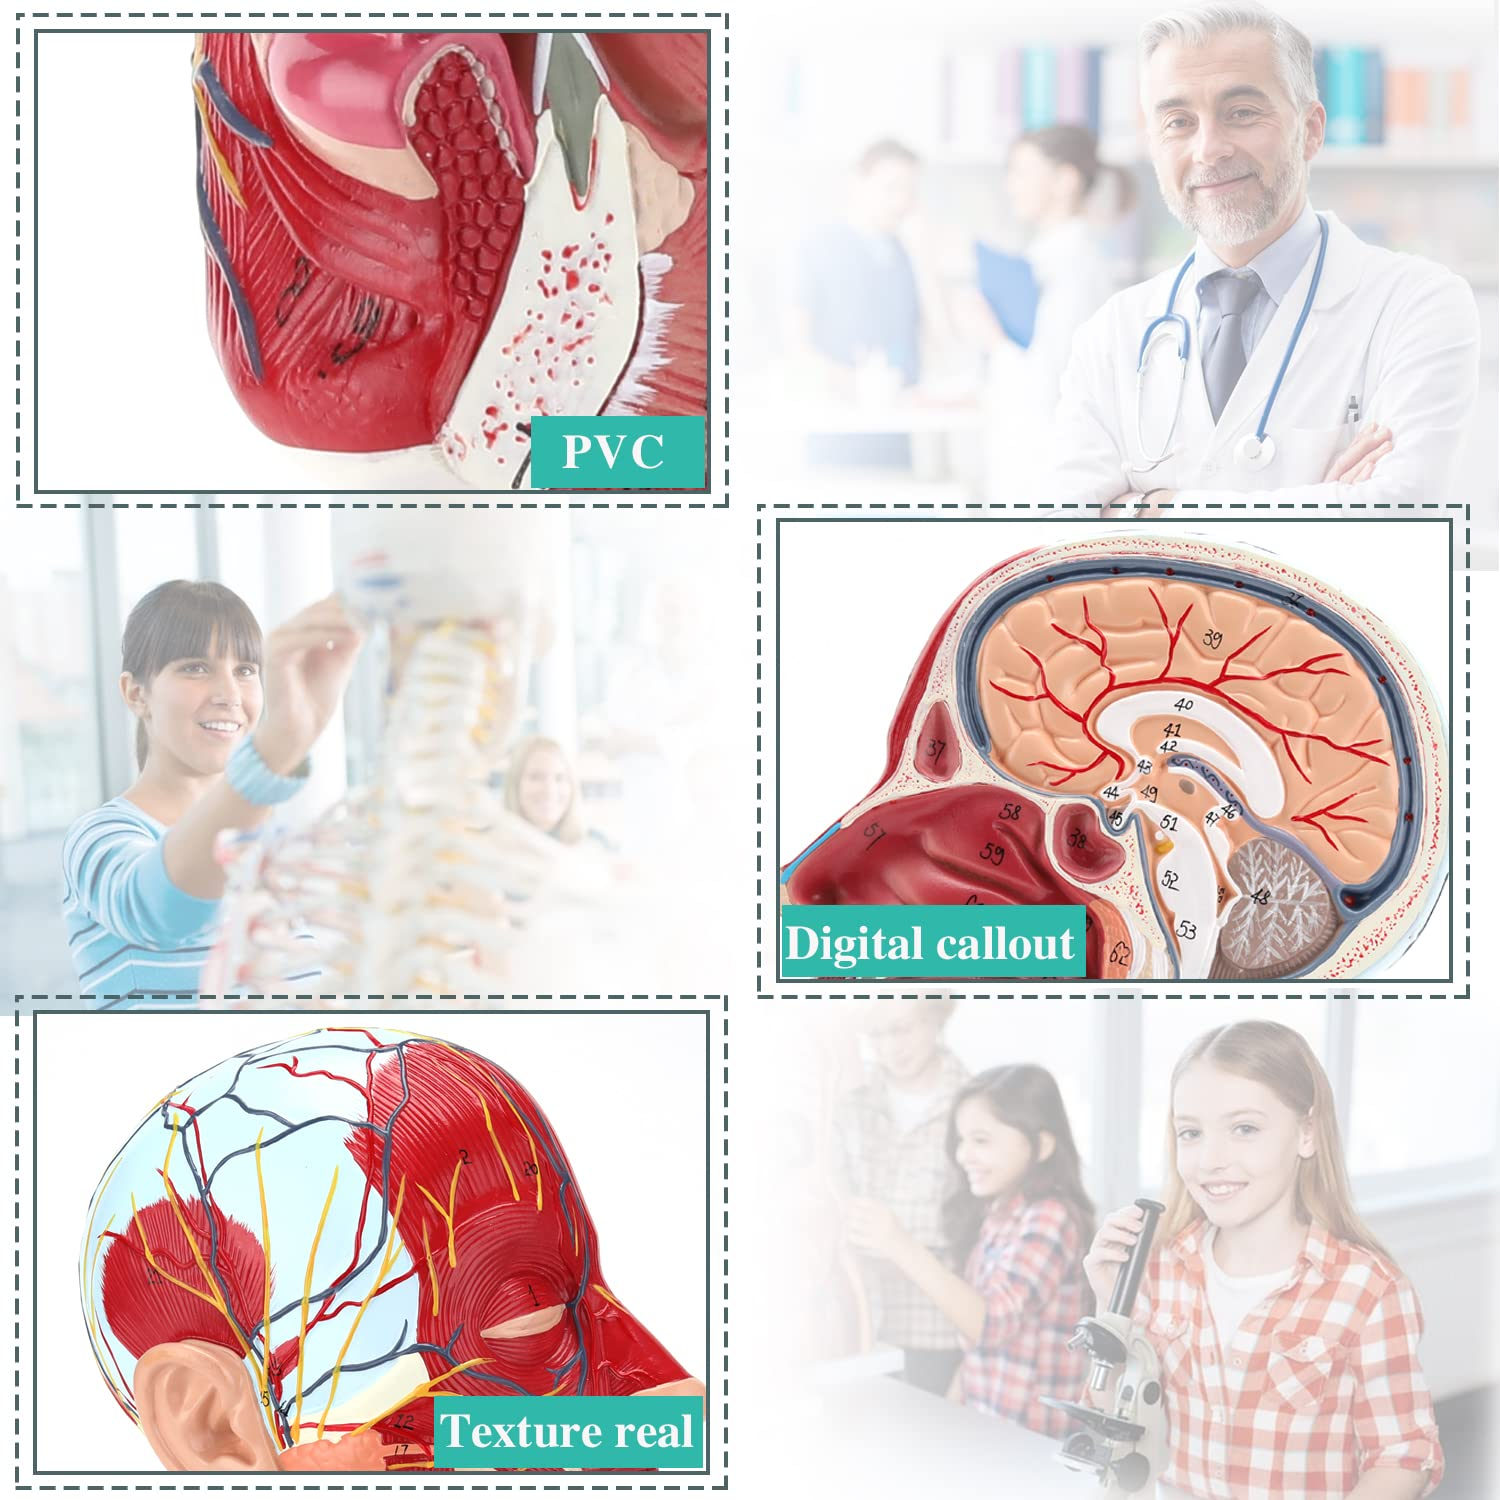

| Oun elo | Pvc |

Didara Anatomin anatomy, ti a ṣe ti kii-majele ayika ohun elo pvc ore, rọrun lati sọ di mimọ. Awọn awoṣe Anatomi ni a gbin ati pejọ pẹlu akiyesi ti o ga julọ si alaye.

Awoṣe iṣan iṣan】 alaye ti o ga pupọ, awọn nọmba ti samisi, jinlẹ ti awọn iṣan to loye awọn iṣan ati ọrun inu & ọrùn ti ori & ọrun. Atter-mq-iṣọn, buluu-vening, alawọ ofeefee.